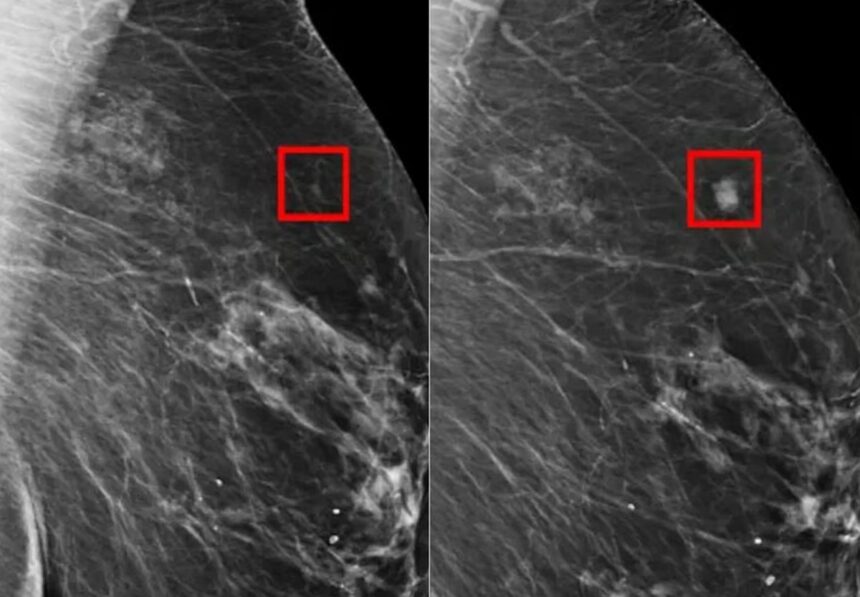

Umelá inteligencia odhalila o deväť percent viac prípadov rakoviny prsníka než štandardný postup s dvoma rádiológmi, ukázala prvá dokončená randomizovaná klinická štúdia na svete, ktorej výsledky zverejnil medicínsky časopis The Lancet.

Švédsky výskumný tím v štúdii sledoval viac ako 100-tisíc žien, ktoré absolvovali bežný mamografický skríning v rokoch 2021 a 2022. Ženy boli náhodne rozdelené do dvoch skupín. V prvej snímky vyhodnocoval jeden rádiológ s pomocou systému umelej inteligencie, v druhej dvaja rádiológovia bez nej, čo je štandardný európsky postup.

Skupina s AI mala počas nasledujúcich dvoch rokov o 12 percent nižší výskyt takzvaných intervalových karcinómov, teda nádorov diagnostikovaných medzi pravidelnými kontrolami. Tie pritom bývajú obzvlášť nebezpečné. Zlepšenie bolo konzistentné naprieč vekovými kategóriami aj rôznymi stupňami hustoty prsného tkaniva. Miera falošne pozitívnych výsledkov zostala v oboch skupinách porovnateľná.